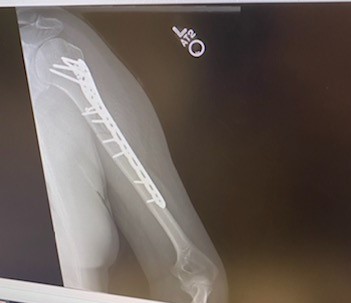

My name is Jayden Cassese and I'm a 12 year old baseball player for the TYA Tigers. In the first pre-season tournament for our big 12U season, I collided with the shortstop sliding into second base and broke off the end of the elbow bone in my left arm. This was the big year for Little League and we had the famous Cooperstown Tournament coming up in July, playing against 100 teams from around the country. I was devastated at the idea of missing that after years of building up to it.

Luckily for us, we knew friends of Dr. Green, and a fellow surgeon at HSS, and both of them strongly recommended we use Dr. Green to repair the elbow. 2 days later I was getting operated on at HSS in Manhattan, and the entire process was handled very well by Dr. Green and his entire staff. After putting 2 pins in my elbow and allowing it several months to heal, while doing PT at HSS along the way, I was able to get back on the field just in time for my big tournament. I came back stronger than ever and hit 2 home runs in one game my first weekend back, then 3 home runs the next week while at Cooperstown! Thank you Dr. Green and team for helping me make it to Cooperstown and beyond.